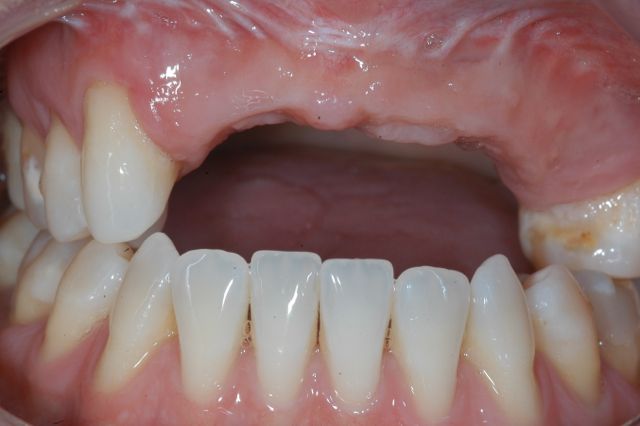

Staged multiple bone grafting and dental implant replacement in a patient with missing upper anterior teeth.